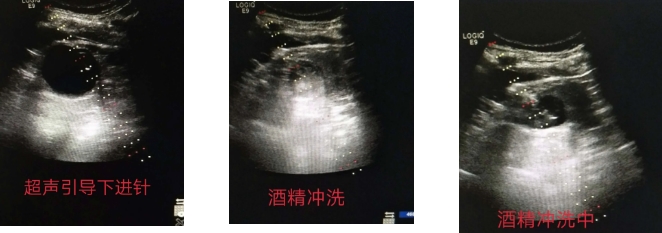

肾囊肿虽是一种常见的良性疾病,但如果囊肿体积较大,则会引起腰部酸胀、不适、疼痛,甚至受外力挤压时,容易造成破裂,出血不止的情况。5月26日,一位60岁的男性丙肝史患者入住淄博市第四人民医院,在正常体检时发现左肾囊肿,囊肿大小5.3×5.2cm。考虑到患者的具体病情,彩超室为其实施了创伤小、疗效好的超声引导下无水酒精硬化治疗。彩超室主任邵宏增和主治医师高珊珊密切配合,精准定位,精确引导,抽得清亮囊液60ml,并注入无水酒精硬化,术后复查超声囊肿消失,患者无明显不适症状,在门诊观察30分钟后,自行走回病房,轻松解决了患者的病痛。

据彩超室主任邵宏增介绍,随着超声介入治疗的开展,利用超声引导下穿刺注射无水酒精治疗肾囊肿已被临床广泛应用。超声引导经皮穿刺治疗肾囊肿具有操作简便、创伤小、疗效显著、安全适用、恢复快等特点。